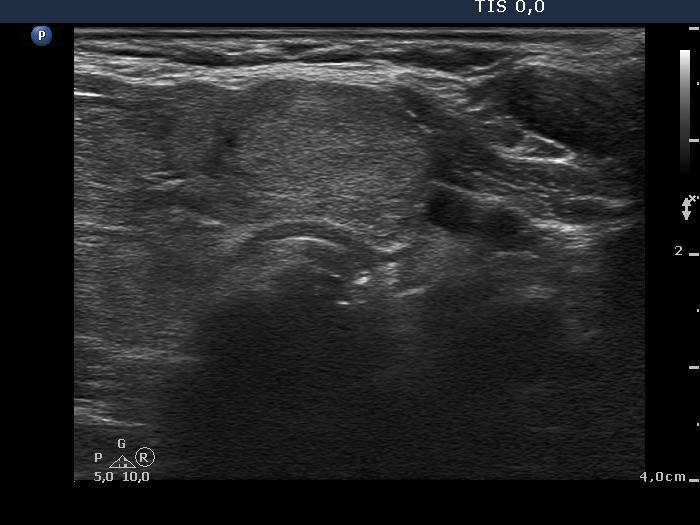

Lymphocytic thyroiditis - case 609 (ultrasonographic picture 5)

Right lobe, longitudinal scan

Isthmus, transverse scan. There is a relatively larger echnormal lesion.